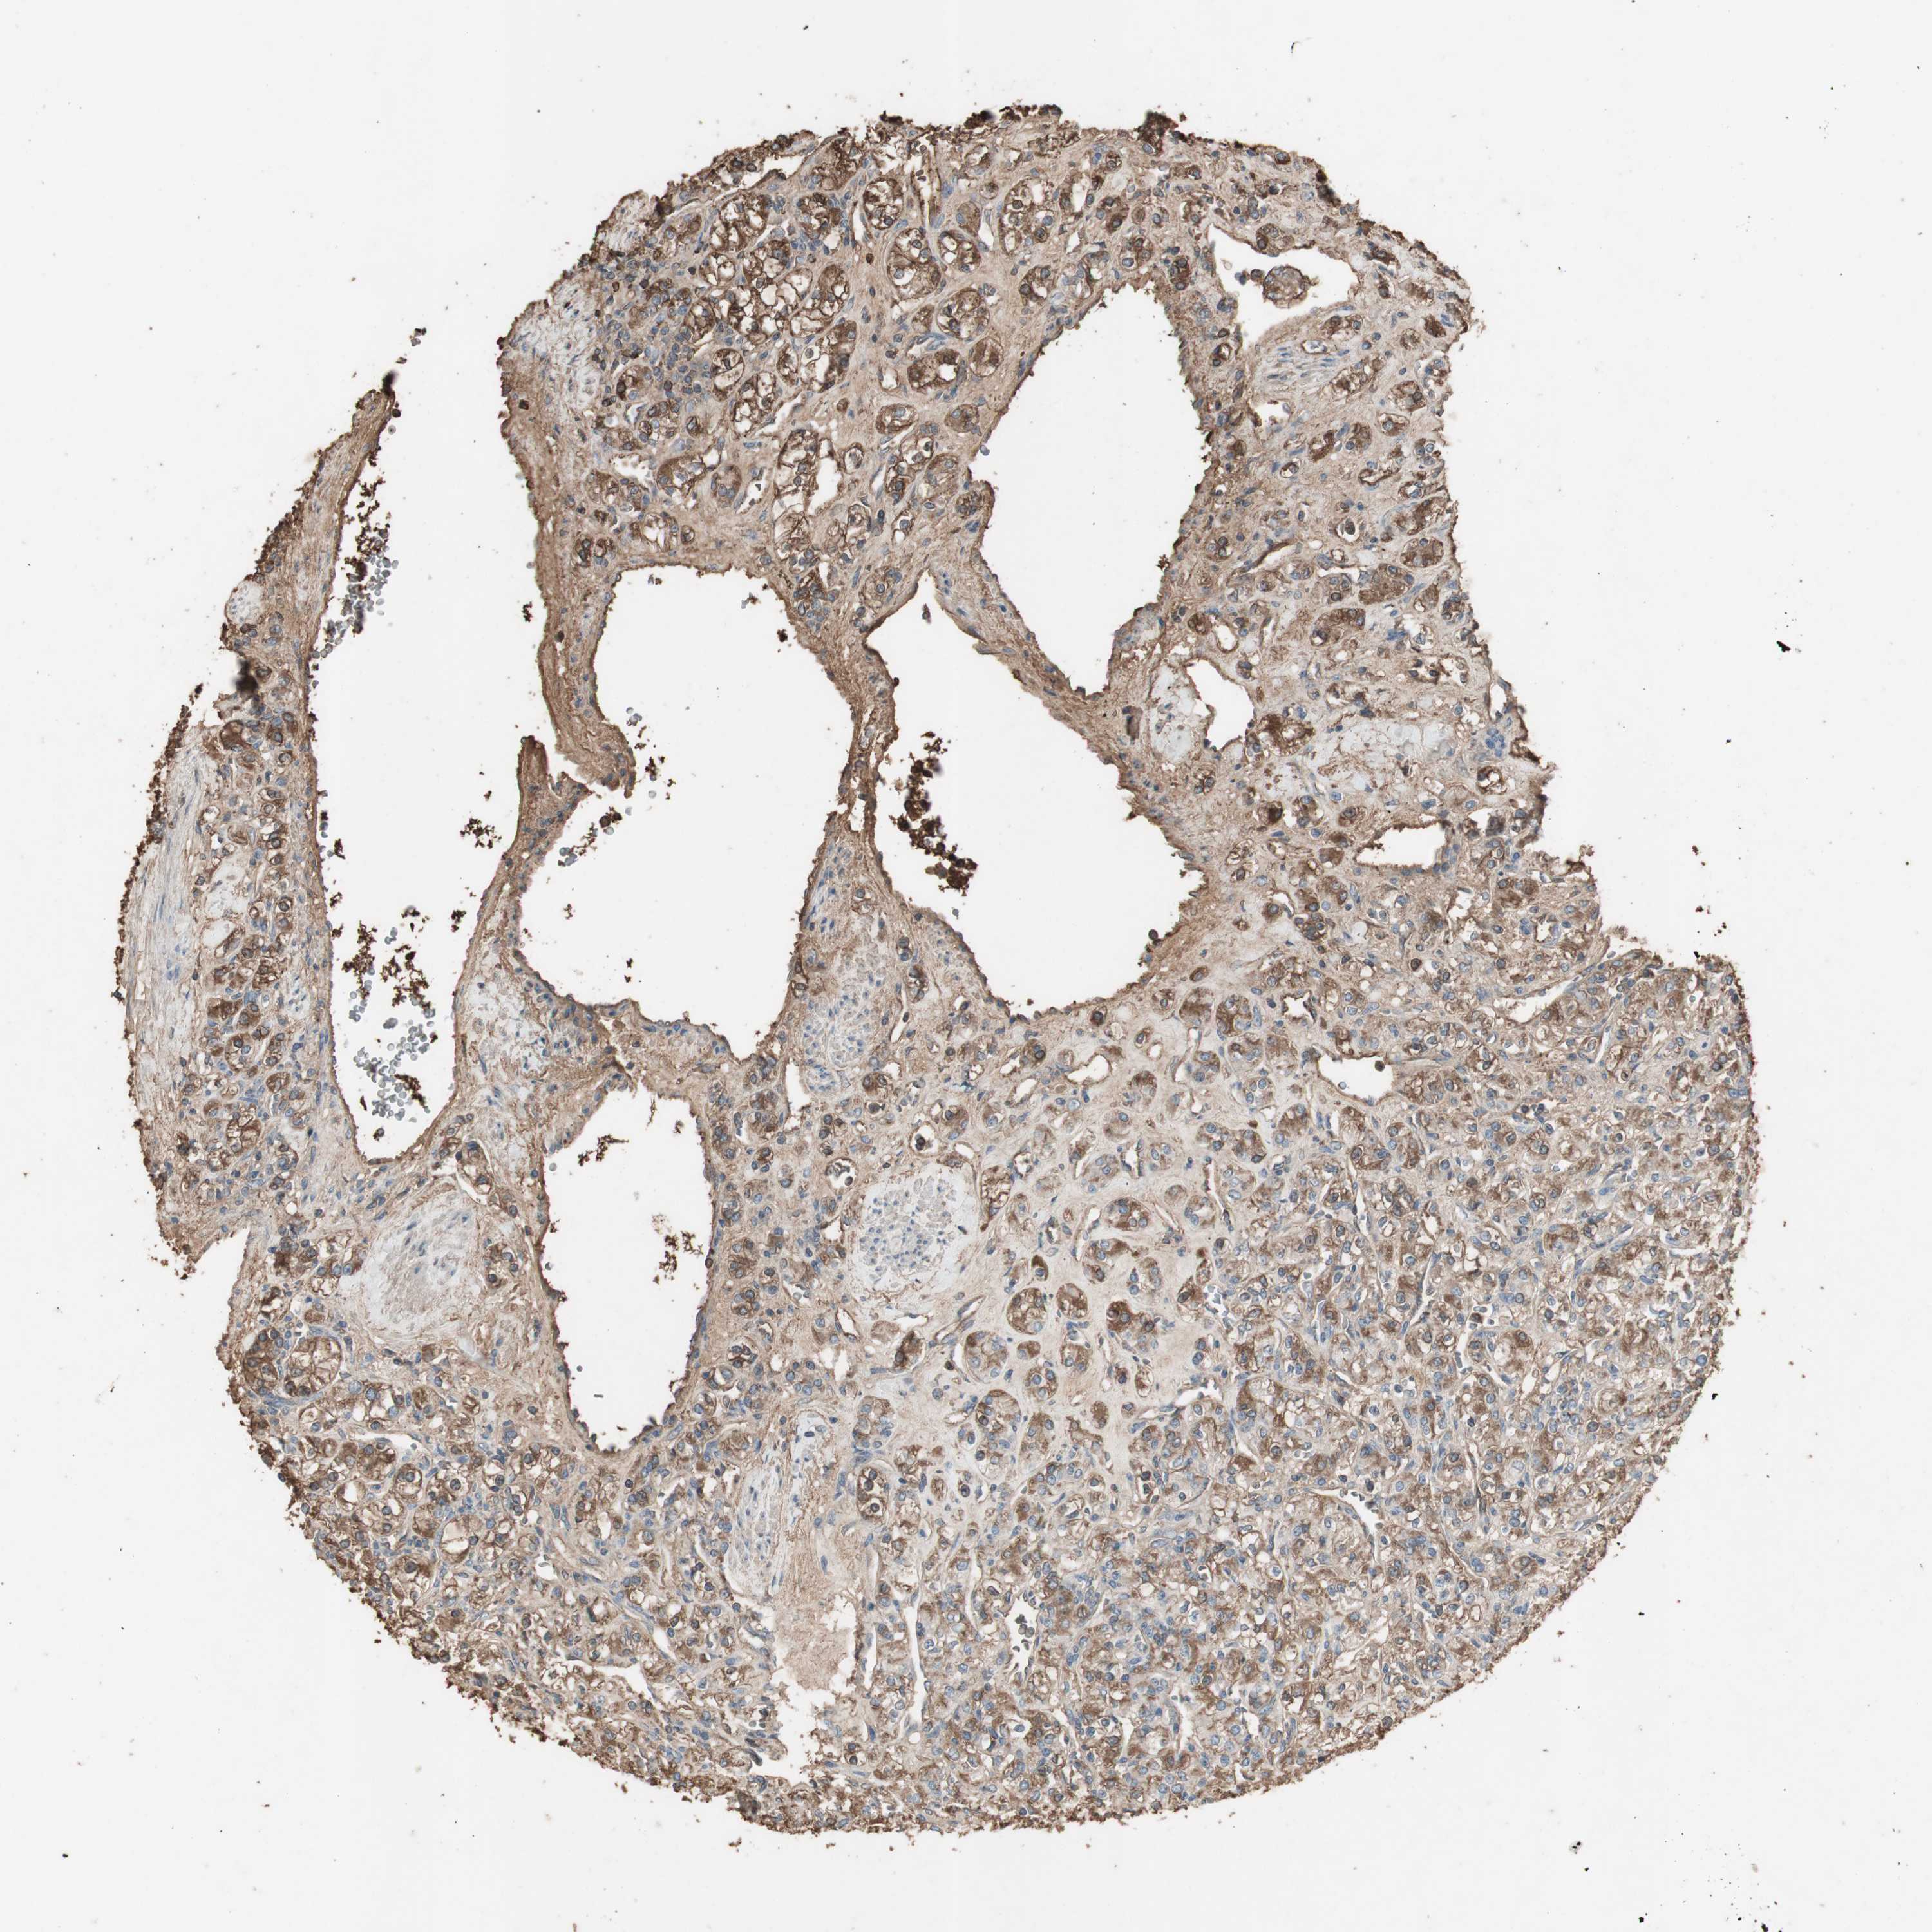

CANCER RENAL CANCER Show tissue menu

KICH TCGA KIRC TCGA KIRC VALIDATION KIRP TCGA PROTEIN RCC CPTAC PROTEIN EXPRESSION

Renal cancer

Kidney renal papillary cell carcinoma

MMP14 is not prognostic in Kidney Renal Papillary Cell Carcinoma (TCGA)